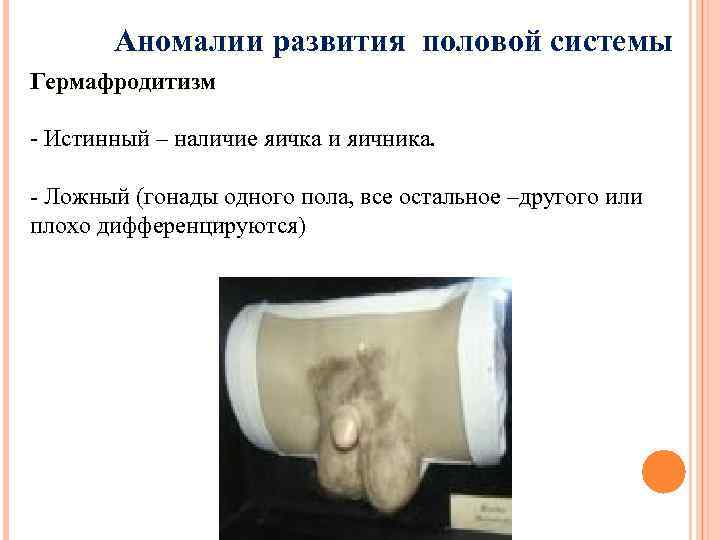

Аномалии развития половой системы Гермафродитизм - Истинный – наличие яичка и яичника. - Ложный (гонады одного пола, все остальное –другого или плохо дифференцируются)

Аномалии развития половой системы Гермафродитизм - Истинный – наличие яичка и яичника. - Ложный (гонады одного пола, все остальное –другого или плохо дифференцируются)